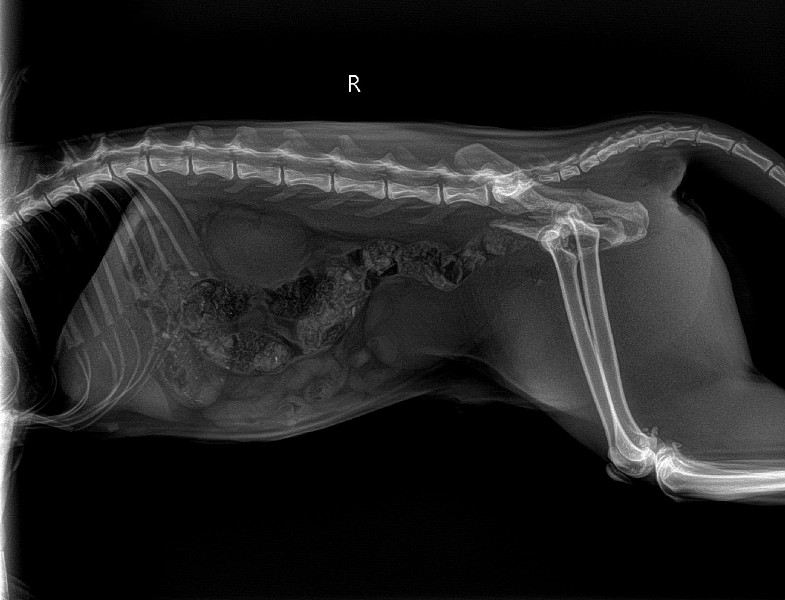

Перелом таза у собаки

Перелом таза у собаки 139 фотографий